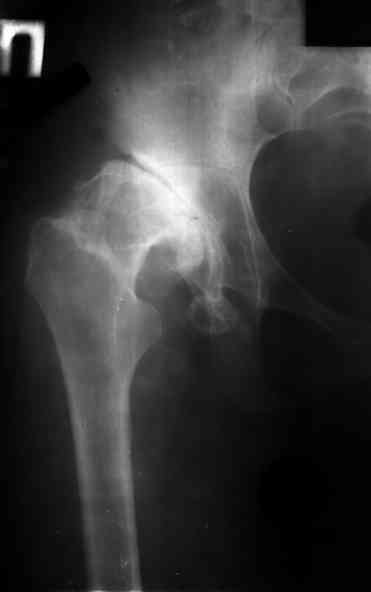

Ув. коллеги, женщина, 37 лет, имеет диспластический коксартроз. Сомневается в положительном результате от эндопротезирования, но хочет оперироваться. Что порекомендуете? С ув. Sergey A. Melashenko ул. Кирова 88-А, г. Приморск, Запорожская обл., 72100, Украина

Оперироваться. Альтернативы нет. Надо делать обе ноги, поочередно с реконструкцией крыш для последующей удобной ревизии. Ножки бесцементные.

Остальное дело техники. С ув. А Рыков. Хабаровск. Мы бы взялись.

Сергей. Операция первичного эндопротезирования предусматривает у данной больной (я бы сделал так) - 1. Доступ с хорошим обзором впадины (или задний

или с пересечением б.вертела) - затем установку тазового компонента с одномоментной пластикой крыши вертлужной впадины из утилизируемой головки

(если получится бесцементная чаша - это лучше, но не факт - вероятно будет моделирующее кольцо с цементируемой чашей - внимание к "версии" чаши) -

затем классическая бесцементная ножка. Справа будет попроще. Слева рассчет после установки правого сустава. Может потребоваться двухэтапное

протезирование. При отсутствии проблем с финансировании - отправьта в Харьков - Киев - Донецк. С уважением. А Рыков.

1. при таком анатомическом варианте корригирующие остеотомии явно проигрывают тотальному эндопротезированию.

2. первым этапом оперируем сторону с преобладающим болевым.

3. справа может быть будет достаточно структурного аутотрансплантата, но вариант с кольцом надо иметь в виду; слева использовал бы армирующую конструкцию (плохая надацетабулярная кость - проблемное приживление трансплантата).

4. вероятность осложнений выше, чем в банальной ситуации, правильно дама беспокоится, лучше делать операцию там, где это на потоке. Если ближе не найдется, присылайте.